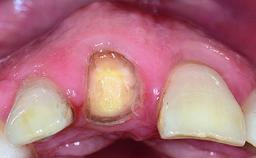

A healthy 37-year-old female patient was referred for a consultation on the replacement of missing tooth 21 with an implant-supported restoration. She stated that several years previously the tooth had been traumatically avulsed following a motor vehicle accident. The tooth was replaced with a three-unit fixed partial denture (FPD) immediately afterwards. Over time, she became disillusioned with the FPD and looked for a different option, including orthodontic therapy. She presented still in her orthodontic appliances, with the pontic sectioned free from the FPD but attached to the archwire. Her orthodontist felt that orthodontic treatment had been successfully completed, but nevertheless referred her before removing the appliances in case adjustments were necessary.

Defining Characteristics One missing tooth to be replaced by an implant-borne prosthesis

Defining Characteristics One missing tooth to be replaced by an implant-borne crown

Retention Cemented, with prosthesis margin < 3mm submucosal Cemented, with prosthesis margin < 3mm submucosal

Esthetic Risk High

Soft Tissue Contour and Volume Slightly compromised